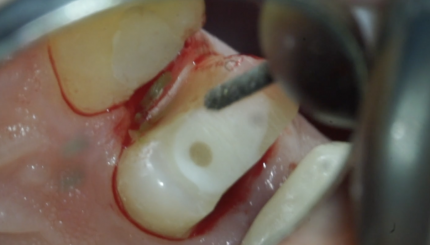

14 зуб. Полная тонкостенная коронка,ретракция,оттиск.